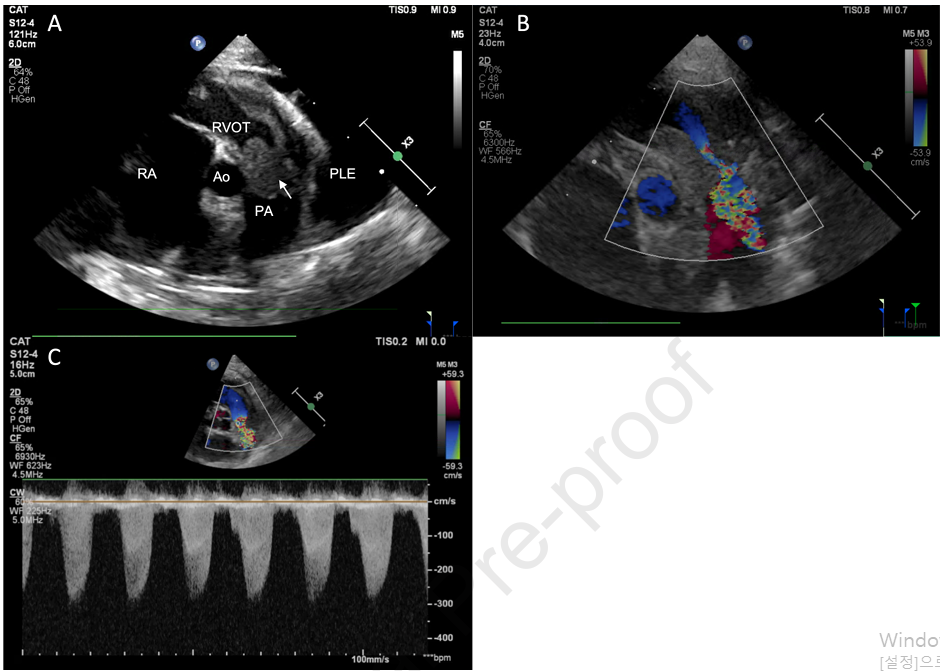

- 초음파 검사 소견: 경흉부 심장 초음파 검사에서 우심실 유출로에 광범위하고 균질한 종괴가 발견되었으며, 이는 폐동맥 판막을 침범하여 심한 유출로 및 판막성 폐동맥 협착증을 유발하였습니다. 이로 인해 우심방 및 우심실 확장이 관찰되었습니다. 또한, 심한 흉수와 미량의 심낭 삼출액, 간정맥 울혈 및 후대정맥 확장이 확인되어 우측 울혈성 심부전과 일치하였습니다.